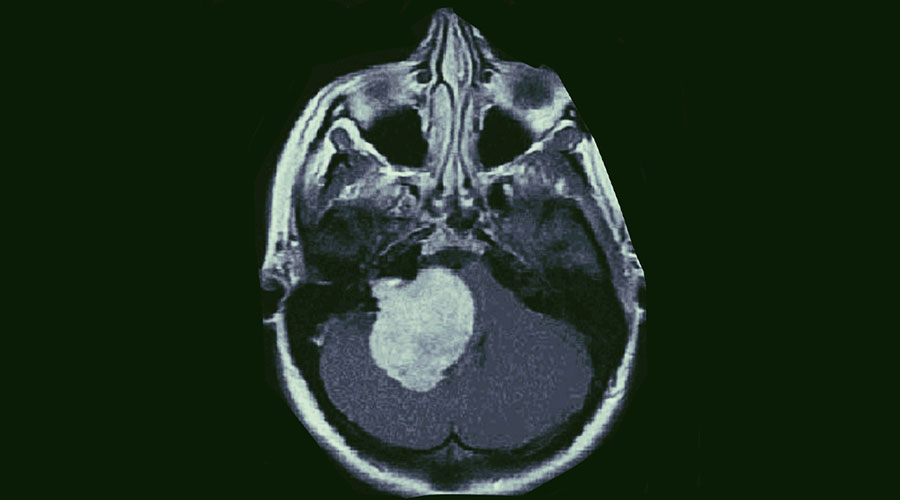

He did his super-specialisation MCh Neurosurgery from SMS medical college and Hospital, Jaipur. SMS medical college, neurosurgery department is one of the largest neurosurgical catering hospital of north India. During his MCh, he gained vast surgical experience of variety of neurosurgical patients of brain and spine tumour, head injury and variety of spinal surgeries. SMS Hospital is one of the very few neurosurgical centres in India that is dedicated to both brain as well as Spine surgery. Working there he had been extensively exposed to spine surgery and developed special interest in endoscopic and minimal invasive spine surgery. He completed his MCh neurosurgery with flying colours. After completing his MCh he had worked in the reputed corporate hospitals like Max Superspeciality Hospital Saket, New Delhi, in post graduate department of neurosurgery with international standards of neurosurgical care, where he further gained vast experience in management of brain tumour patients using neuronavigation (the best imaging modality to localize the tumour intraoperatively) and use of intraoperative CT scan and intra-operative ultrasound.

Very efficient neurosurgeon. My patient for brain tumor was operated, patient is doing fine. Thanks a lot